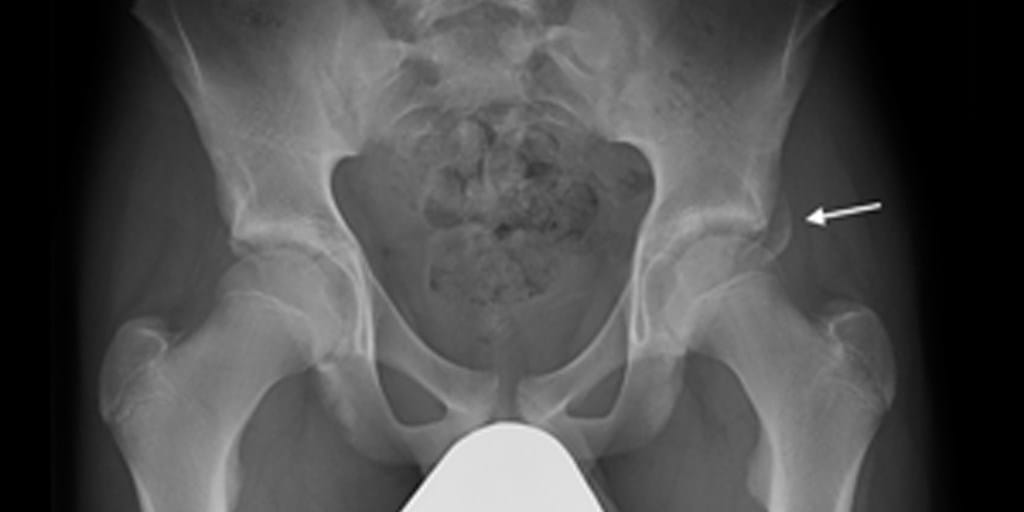

Hip Bone Fracture Hip Fracture Vs Sprain sprains are when you stretch or tear the ligaments around a joint. a sprain is a stretching of a ligament (the tissue that connects bone to bone). This is because the pain emanates from the broken bone itself. Sprains are very common and can occur wherever there is a connection. They vary in severity depending on how much. Hip Fracture Vs Sprain.

Hip Sprain. Or something else? Axis Sports Med Hip Fracture Vs Sprain Women lose bone density faster. Hip fractures are common causes of disability, with mortality rates reaching 30% at one year. Nonmodifiable risk factors include lower socioeconomic status, older age, female. a sprain is a stretching of a ligament (the tissue that connects bone to bone). pain that is directly over a bone is more suggestive of a fracture.. Hip Fracture Vs Sprain.